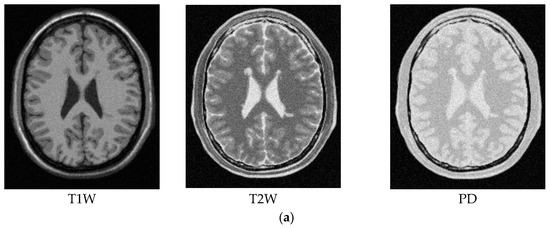

For an illustrative purpose, Figure 5, Figure 6, Figure 7, Figure 8, Figure 9 and Figure 10 only show detection results of WMH lesions of the 97th MR image slice with six levels of noise and 0% INU by two versions of CBEP-ICEM, using the Gaussian window size of specified by σ = 0.1 and the Gaussian window size of specified by σ = 0.5, referred to as CBEP-ICEM1 and CBEP-ICEM2, respectively, where two sets of training samples selected by all slices and the single 102nd slice were used to calculate the desired target signatures d to implement NBE-ICEM. As we can see by visual inspection against the ground truth in Figure 4d, CBEP-ICEM1 and CBEP-ICEM2 using two sets of training samples, i.e., all slices-selected and single slice-selected training samples, produced very close results and they both also performed better lesion detection than LST did.

Lesion detection of Slice 97 with 0% noise and 0% INU by CBEP-ICEM1 and CBEP-ICEM2. (a) CBEP-ICEM1; (b) CBEP-ICEM2; (c) Lesion detection LST.

Figure 6.

Lesion detection of Slice 97 with 1% noise and 0% INU by CBEP-ICEM1 and CBEP-ICEM2. (a) Original 97th slice of MS MR brain images with 1% noise and 0% INU; (b) CBEP-ICEM1; (c) CBEP-ICEM2; (d) Lesion detection LST.

Figure 7.

Lesion detection of Slice 97 with 3% noise and 0% INU by CBEP-ICEM1 and CBEP-ICEM2. (a) Original 97th slice of MS MR brain images with 3% noise and 0% INU; (b) CBEP-ICEM1; (c) CBEP-ICEM2; (d) Lesion detection LST.

Figure 8.

Lesion detection of Slice 97 with 5% noise and 0% INU by CBEP-ICEM1 and CBEP-ICEM2. (a) Original 97th slice of MS MR brain images with 5% noise and 0% INU; (b) CBEP-ICEM1; (c) CBEP-ICEM2; (d) Lesion detection LST.

Figure 9.

Lesion detection of Slice 97 with 7% noise and 0% INU by CBEP-ICEM1 and CBEP-ICEM2. (a) Original 97th slice of MS MR brain images with 7% noise and 0% INU; (b) CBEP-ICEM1; (c) CBEP-ICEM2; (d) Lesion detection LST.

Figure 10.

Lesion detection of Slice 97 with 9% noise and 0% INU by CBEP-ICEM1 and CBEP-ICEM2. (a) Original 97th slice of MS MR brain images with 9% noise and 0% INU; (b) CBEP-ICEM1; (c) CBEP-ICEM2; (d) Lesion detection LST.